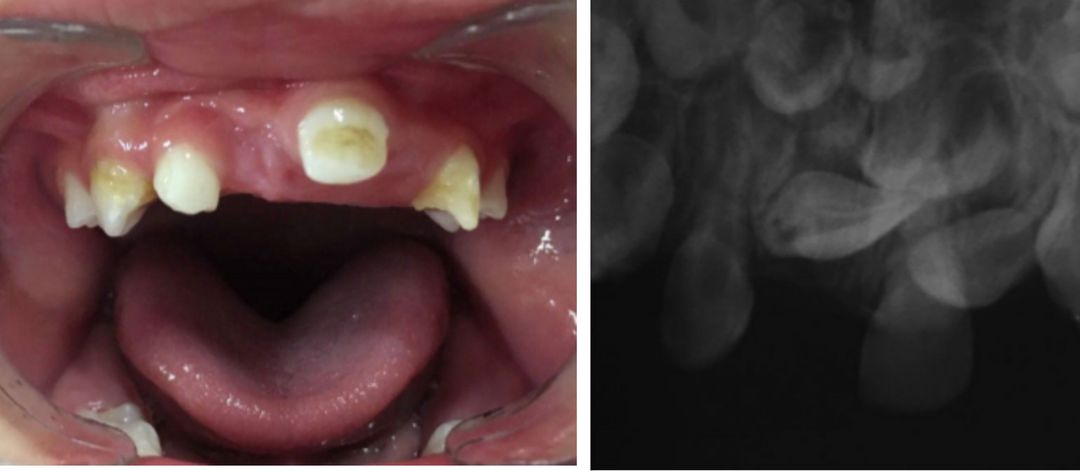

The picture above shows the oral cavity of a 2-year-old boy, presented with complaint of non-eruption of few teeth, as explained by his mother. Detailed developmental history was taken to rule out developmental disorder. The child was born at term through natural delivery and the birth weight was normal. There was no complication during antenatal, perinatal, and postnatal period. The child was vaccinated. Past medical history revealed prior maxillofacial trauma secondary to fall from height at the age of 6 months. Even though, the child was taken to hospital immediately, no examination of oral cavity was varied out at that time. Oral examination and investigations revealed defects ranging from root dilaceration to defects of enamel in few teeth. The non-erupted secondary teeth also showed malformation and odontomas. Management plan consisted of surveillance and periodic dental visits. Surgical intervention was also considered. Excisional biopsy was carried out for suspected odontoma. Source Rare dental developmental disturbance in primary and permanent teeth following trauma prior to tooth eruption: Case report https://onlinelibrary.wiley.com/doi/abs/10.1111/edt.12500 Image via https://onlinelibrary.wiley.com/doi/abs/10.1111/edt.12500